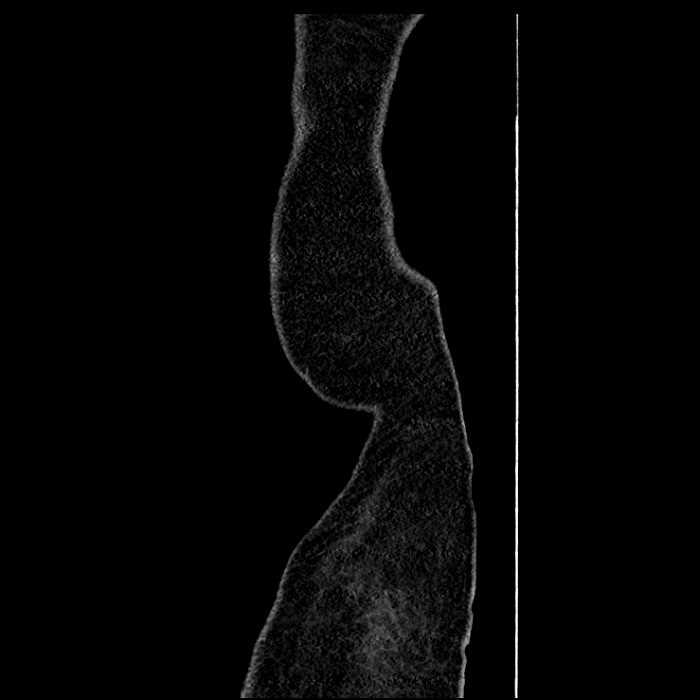

• High grade stenosis of the left common iliac artery, with the left internal and external iliac arteries remaining patent

High grade stenosis of the left common iliac artery. The left external and internal iliac arteries are patent.

Hepatic abscess showing the double target sign with low density internally surrounded by a thin inner enhancing rim (red arrow) and ill-defined outer low density rim (yellow arrow). Blue arrow indicates an internal septation. Red arrows: additional smaller subcapsular abscesses. Red arrow: focal contained perforation associated with diverticulitis.